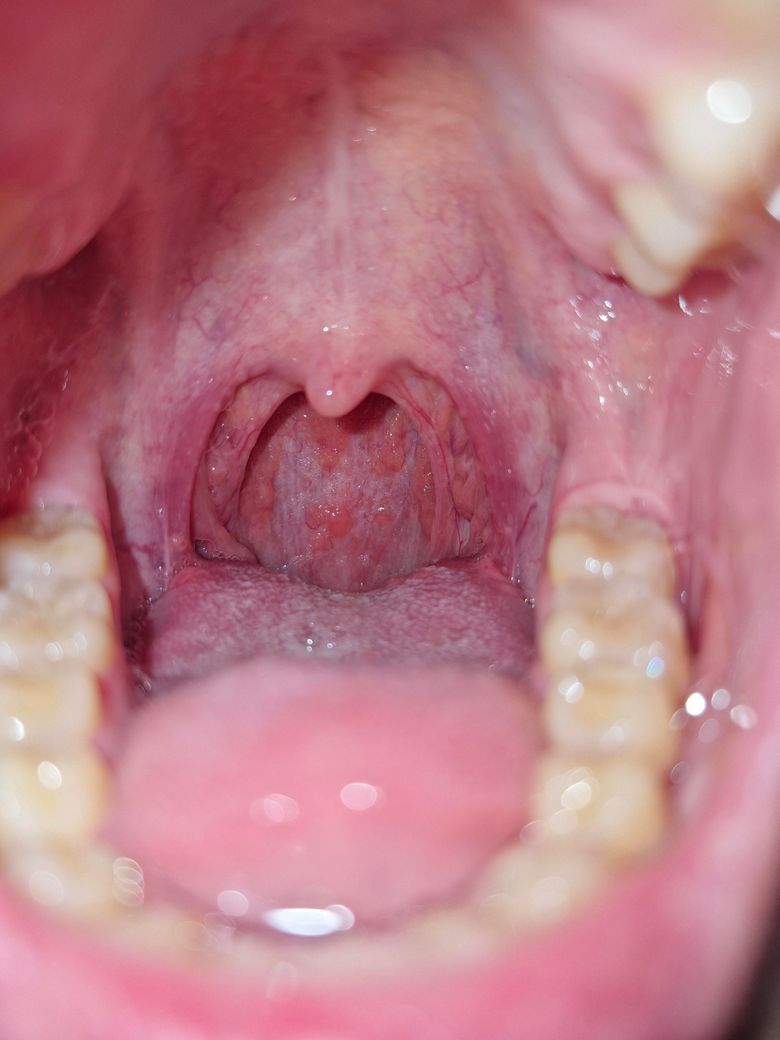

입안 백반증인가요? 한번봐주세요 ㅠ

생긴지는 꽤 됐는데 그냥 다들 그런가보다 하고 살았는데, 급 걱정이 돼서요. 근데 몇개월째 인후통이 간간히 있고 혀 안쪽이 아파서요... 입이 전체적으로 빨간기가 있습니다 ㅠㅠ넘 걱정돼요

사진상에 보이는건 백반증은 아니고 오히려 인후통은 편도에 문제 때문에 생긴거 같습니다.

백반증으로 보이지는 않으나 구내염으로 보입니다. 우선 소독용 헥사메딘 가글액으로 가글하여 관리하여 주길 권하며, 빨간기와 통증, 그리고 몇 달 이상 지속되는 인후통은 자세한 검사가 필요로 됩니다.